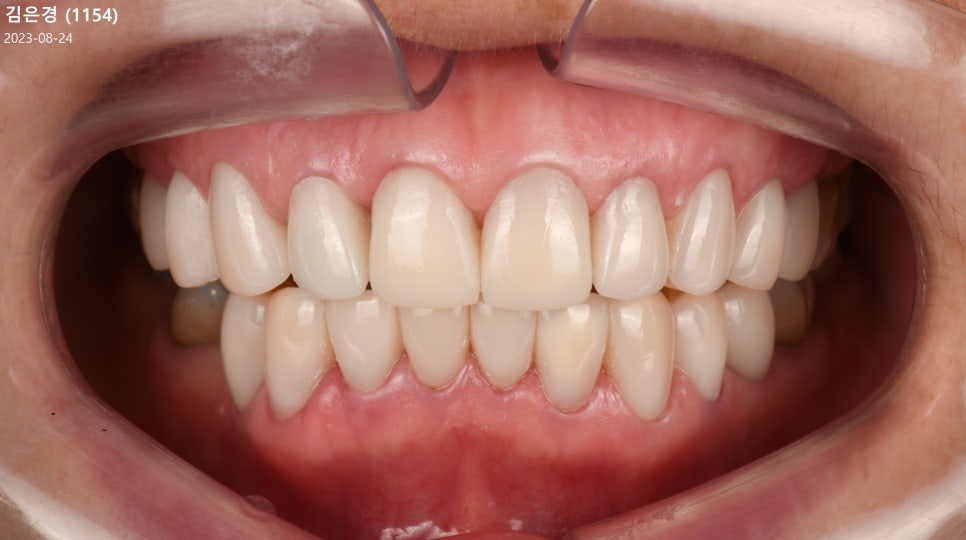

치료 후 모습을 촬영하여 보여드리자면

전과 달리 밝아진 색조를 가지게 됐고,

과하게 물리는 Deep bite 형태의 보철에서

조화로운 크기를 가지며 심미가 높아졌습니다.